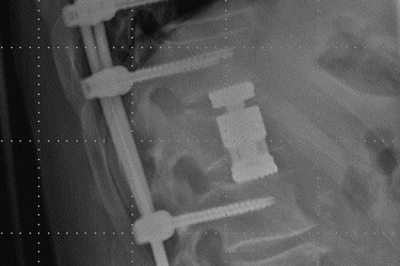

Röntgenbild verschraubter Wirbelbruch. Seitliche Ansicht

Versorgung mit Schrauben-Stab-System und Ersatz des Bandscheibenfaches